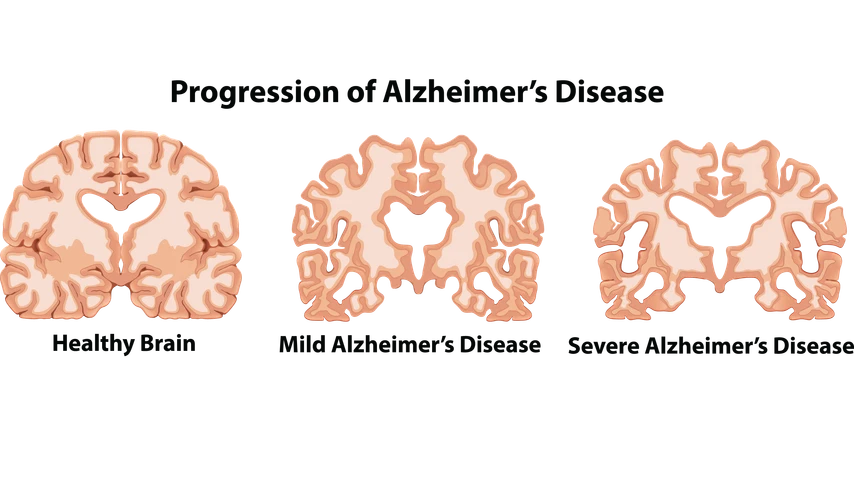

Dementia is a broad term that is used to describe a group of illnesses that negatively impacts the function of the brain. Some forms of dementia include Alzheimer’s disease, vascular dementia, lewy body disease, alcohol-related dementia, younger-onset dementia and many more. Alzheimer’s disease is a progressive degenerative illness that damages the brain. It is caused by amyloid plaques deposits and neurofibrillary tangles that lead to the death of the brain cells. The amyloid plaques inhibit the brain from sending messages or signals and the neurofibrillary tangles prevent the brain cells from receiving nutrients and energy, resulting in their death. The death of the brain cells causes shrinking of the outer layer of the brain which is the area responsible for memory, language and judgement.

The symptoms of dementia depend on what the cause of it is because there are many causes of dementia. The early signs of dementia may not be obvious and may take a long time to be noticed. On the other hand, the symptoms of Alzheimer’s disease are more specific. Alzheimer’s disease normally begins slowly and the symptoms get increasingly worse as time goes on. The stages of Alzheimer’s disease progress from mild to moderate to severe.

As Alzheimer’s disease progresses, the symptoms become severe. Symptoms include: